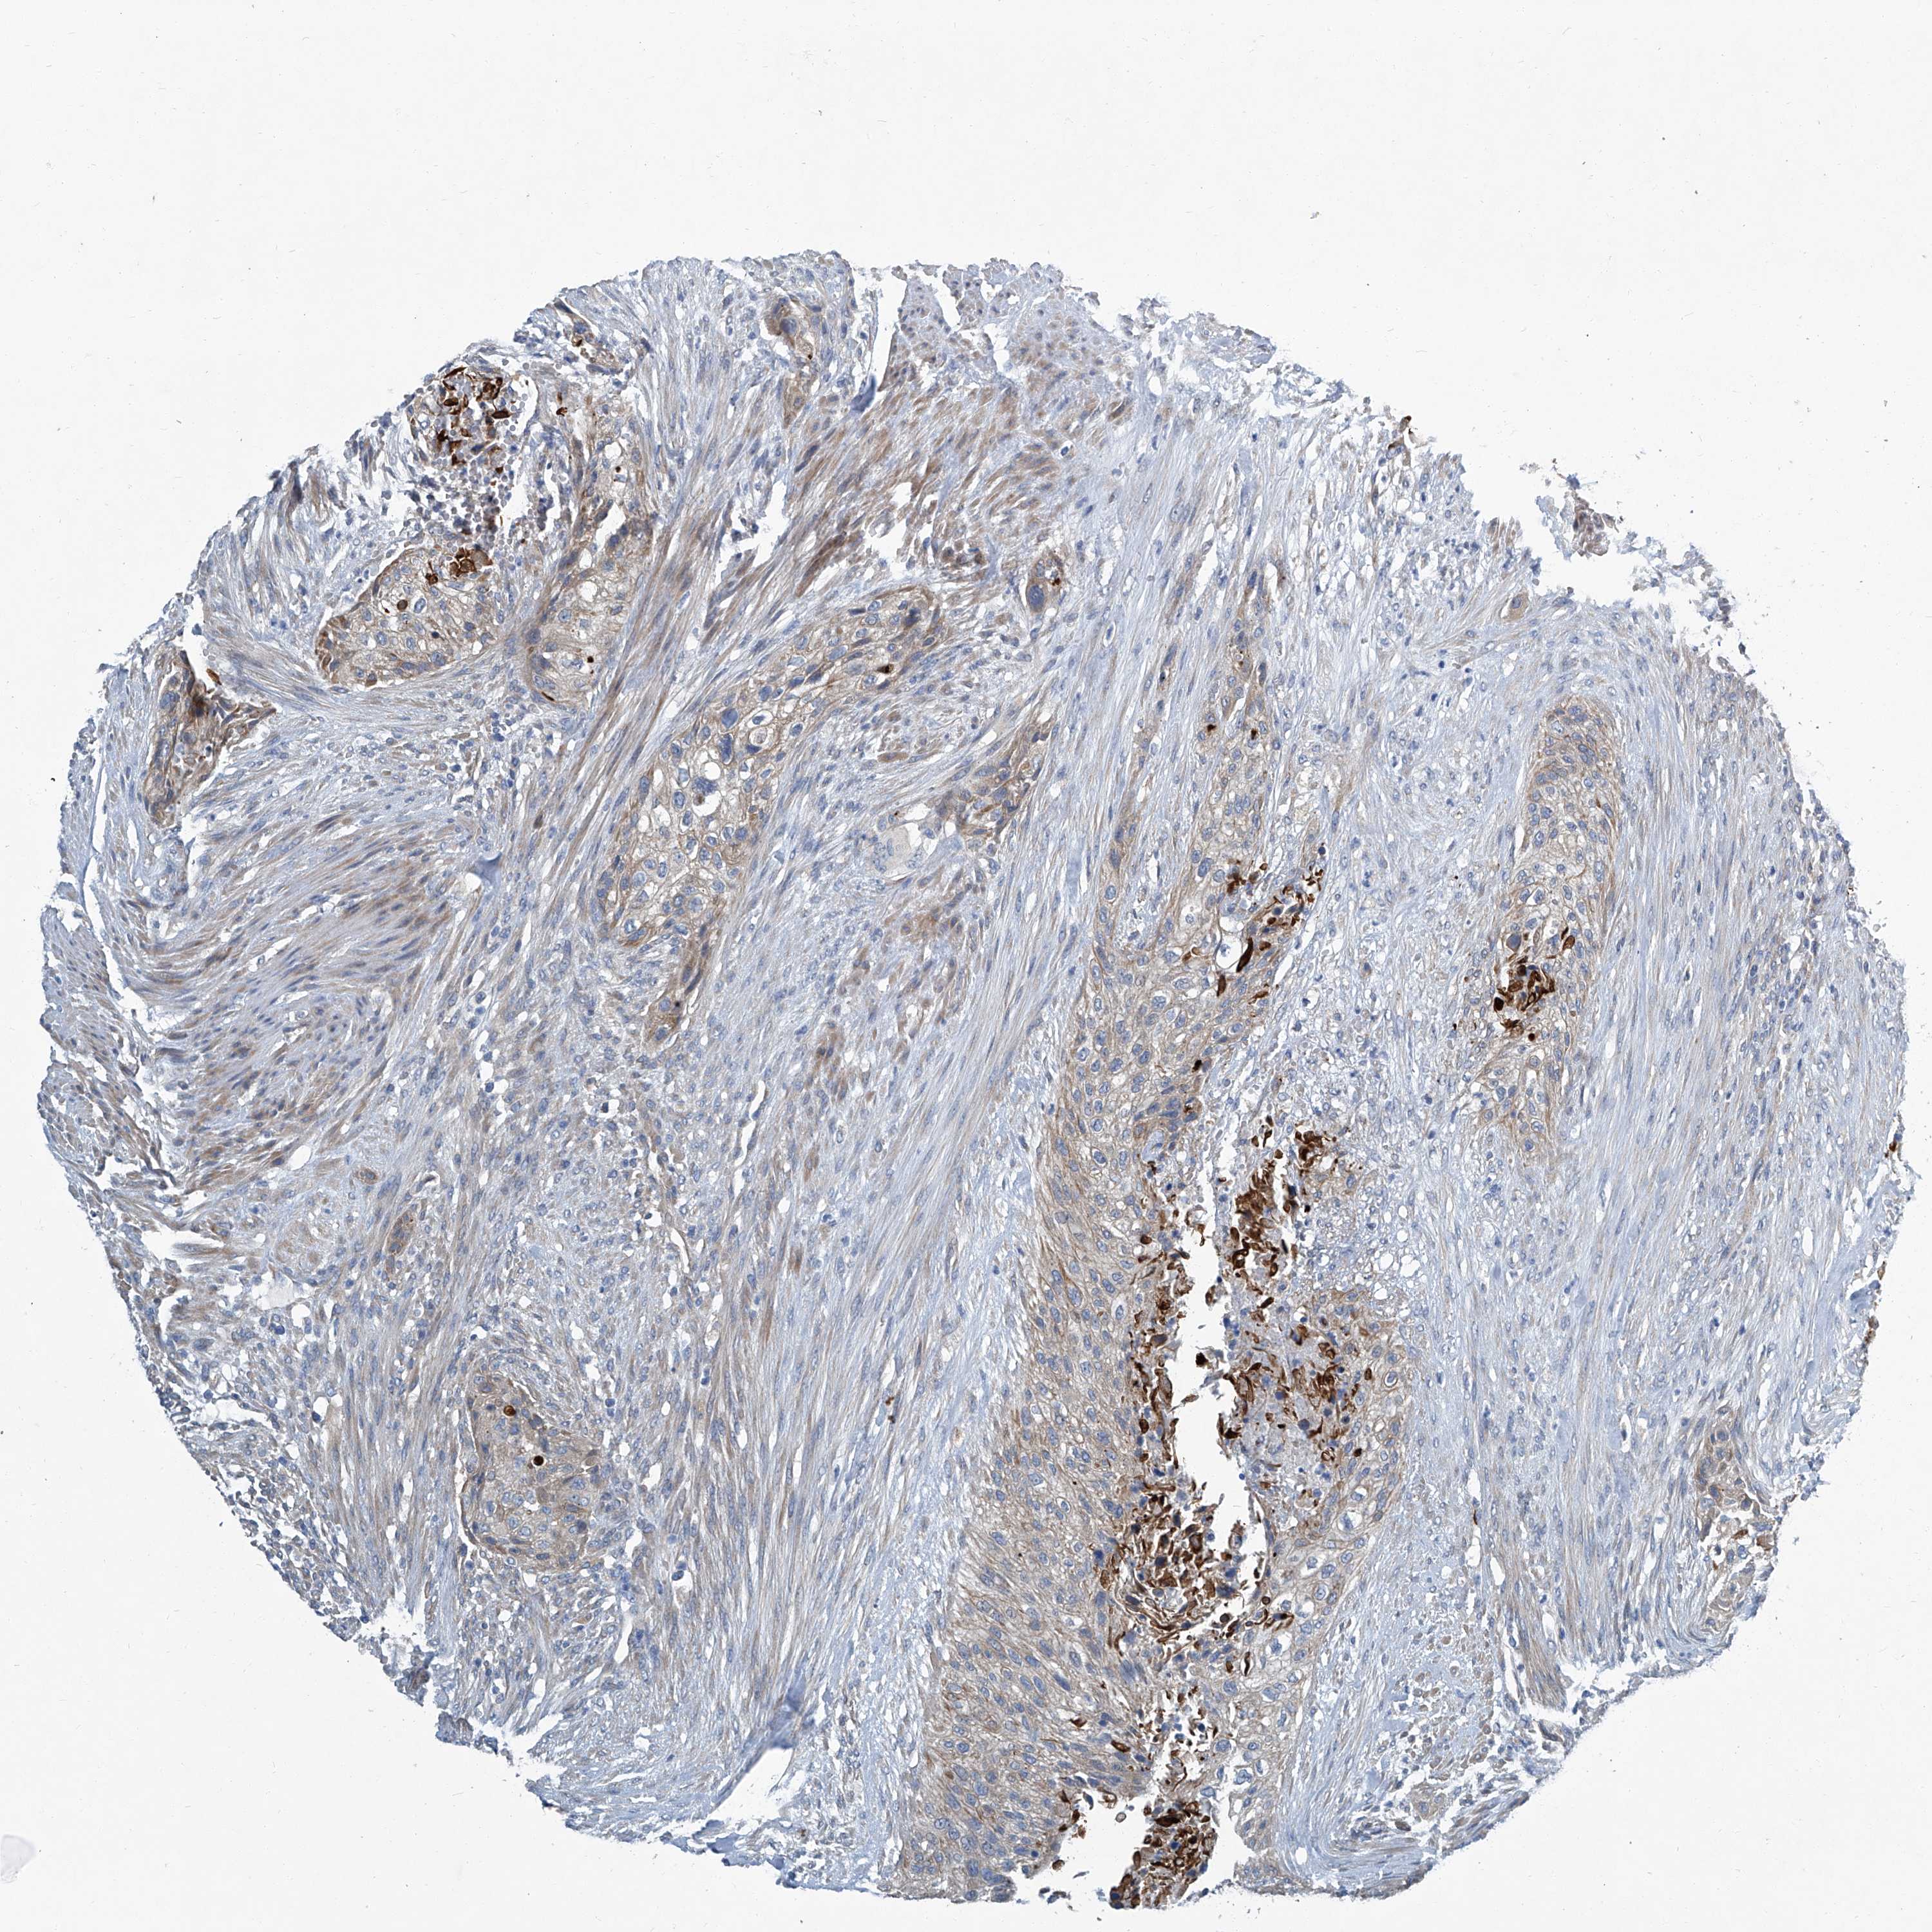

UROTHELIAL CANCER - Protein expressioni

A mouse-over function shows sample information and annotation data. Click on an image to view it in a full screen mode. Samples can be filtered based on level of antibody staining by selecting one or several of the following categories: high, medium, low and not detected. The assay and annotation is described here.

Note that samples used for immunohistochemistry by the Human Protein Atlas do not correspond to samples in the TCGA dataset.

Antibody stainingi

Antibody staining in the annotated cell types in the current human tissue is reported as not detected, low, medium, or high, based on conventional immunohistochemistry profiling in selected tissues. This score is based on the combination of the staining intensity and fraction of stained cells.

Each image is clickable and will lead to virtual microscopy that enables deeper exploration of all samples and also displays staining intensity scores, fraction scores and subcellular localization as well as patient and tissue information for each sample.

Antibody HPA029893

Staining

High

Medium

Low

Not detected

Intensity

Strong

Moderate

Weak

Negative

Quantity

>75%

75%-25%

<25%

None

Location

Nuclear

Cytoplasmic/membranous

Cytoplasmic/membranous,nuclear

Urothelial carcinoma, Low grade

Urothelial carcinoma, High grade